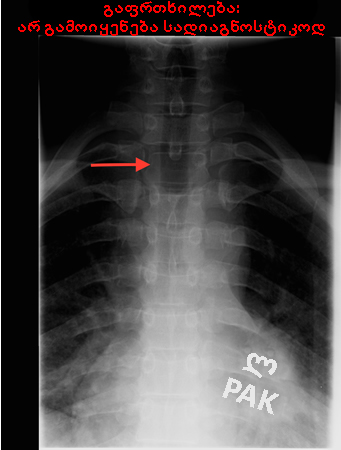

ხერხემლის რენტგენი: "winking owl" (ბუ, რომელიც თვალს გვიკრავს) ნიშანი (ხერხემლის ასიმეტრია, რაც გამოწვეულია მალის რკალის ფეხის დესტრუქციით

ექიმ Dr D. Park-ის საკუთრება; გამოყენებულია ნებართვით